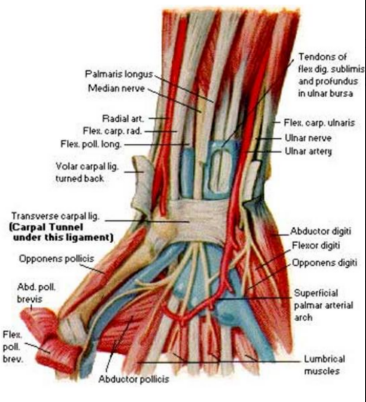

Flexor retinaculum

Fibrous band which bridges anterior concavity of carpals and creates a tunnel

Attachment

Medially- pisiform bone and hook of hamate

Laterally- tubercle of scaphoid and crest of trapezium

Structures superficial

Tendon of palmaris longus

Palmar cutaneous branch of median and ulnar nerve

Ulnar vessels

Structures deep

Median nerve

Ulnar bursa

Tendons of FDS, FPL, FDP

Carpal tunnel syndrome

Intrinsic muscles of hand

Four thenar muscles

Abductor pollicis brevis

Flexor pollicis brevis

Opponens pollicis brevis

Adductor pollicis brevis

Four hypothenar muscles

Palmaris brevis

Abductor digiti minimi

Flexor digiti minimi

Oppenens digiti minimi